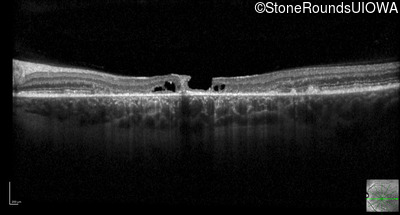

Optical Coherence Tomography - Right - 20/125 -1

Exemplar / OCT Stack